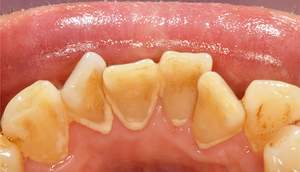

歯石除去

治療前

治療後

| 年齢 | 36歳・男性 |

|---|---|

| 主訴 | 歯石をとりたい |

| 治療内容 | 歯石除去 |

| 治療期間 | 30分 |

| 費用 | 約2,000円 |

| リスク・副作用 | ・歯ぐきの炎症が強いと歯石を取る際に出血することがあります。 ・処置後に歯がしみることがあります。 ・歯と歯の間に隙間ができるので、息が漏れ発音しにくいと感じることがあります。 ・歯ぐきの炎症が軽減すると歯ぐきが引き締まり、歯が長く見えることがあります。 |